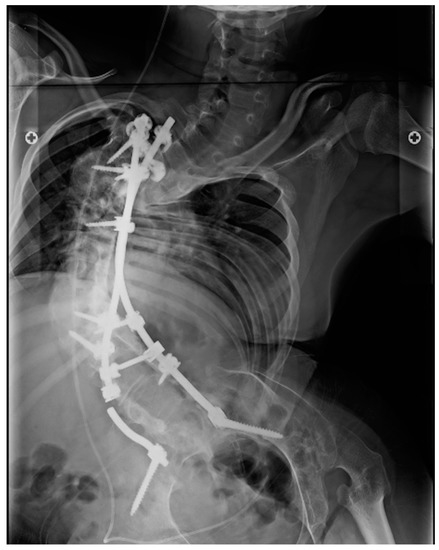

The ability to ambulate is a protective factor against material failure (RR, 0.27), and patients with neuromuscular scoliosis, excluding cerebral palsy as an etiology, are 3.33 times more likely to have mechanical failure than patients with idiopathic scoliosis (example, Figure 2). This fact agrees with previous findings in the literature, in which patients with neuromuscular scoliosis or who do not ambulate have higher rates of complications than those with idiopathic or congenital scoliosis [21,22,23]. Possible explanations for this fact are greater curve severity, poorer bone quality and nutrition, lower muscle mass, less subcutaneous and skin coverage, and more unfavorable clinical aspects, such as poor ventilatory function and recurrent infections, among other factors [24].

Figure 2.

Anteroposterior X-ray showing rod breakage on the right.